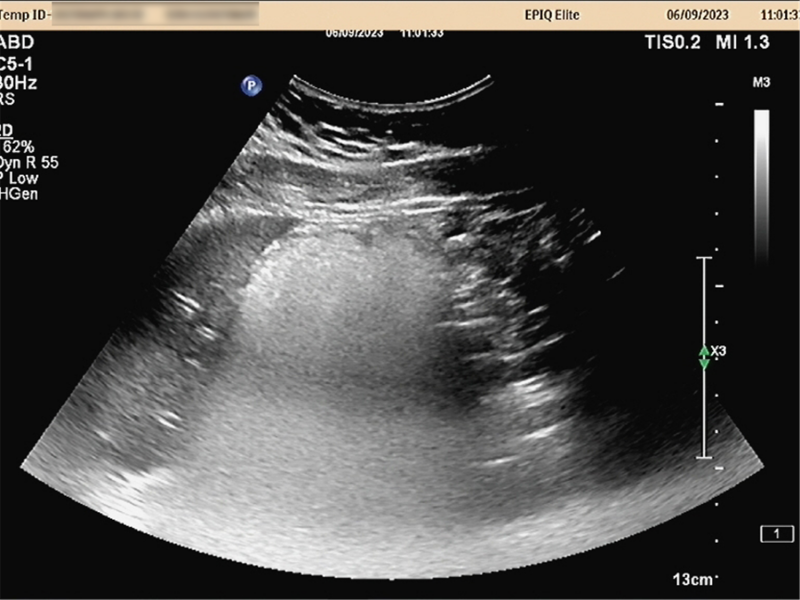

胃充盈超声图像。

烟台山医院超声诊断科主任姜淑燕表示,胃充盈超声检查可了解受检者胃的整体情况,如形态大小是否正常,腔内有无潴留以及充盈和排空情况;了解胃壁层次结构是否正常,有无典型溃疡;还可发现胃粘膜的病变,可观察胃壁内、胃壁外的一些病变。而且能清晰显示胃粘膜下肿瘤,观察肿瘤的内部结构特征及病变范围、浸润程度,进行肿瘤TNM分期诊断,并能显示周围脏器的病变。